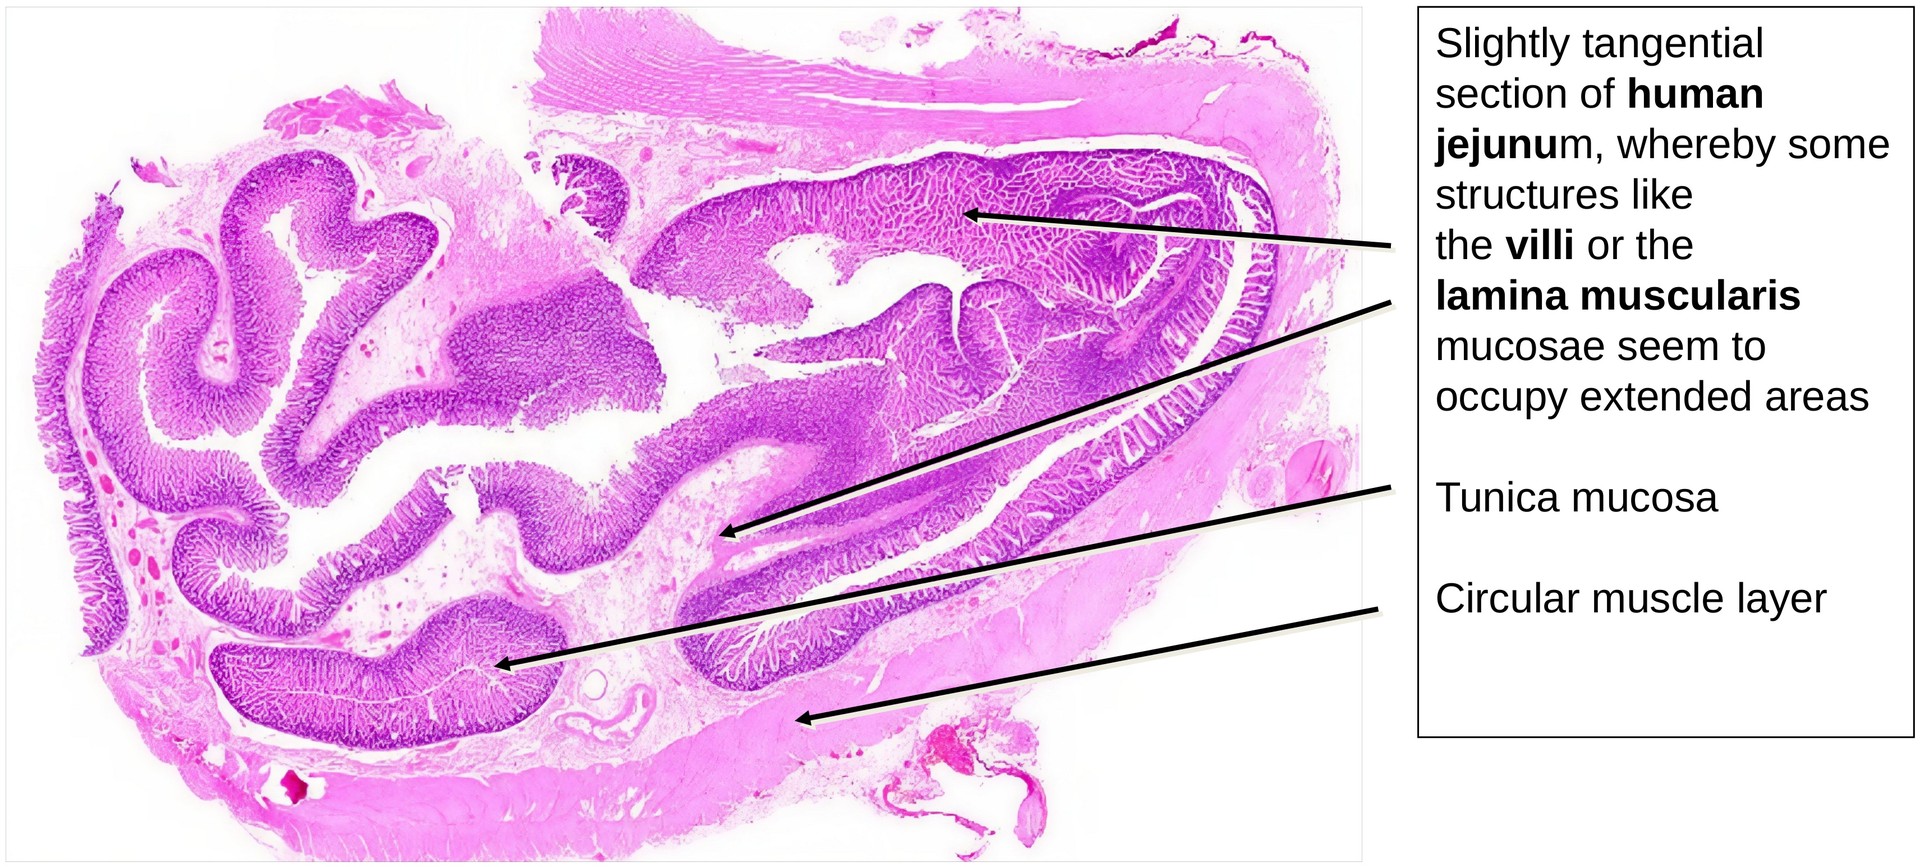

Normal histological specimen stained with H&E, a general overview stain that clearly highlights Paneth cell granules in the crypts. The section is tangential in parts, which makes certain layers—such as the lamina muscularis mucosae—appear planar in places.

The jejunum shows the characteristic structure of the GIT, consisting of the following layers: - Tunica mucosa (with the lamina epithelialis, lamina propria, and lamina muscularis mucosae) - Tela submucosa (containing the submucosal plexus) - Tunica muscularis (composed of inner circular and outer longitudinal muscle layers)

The lamina propria forms a relatively thin layer beneath the epithelium. The lamina muscularis mucosae is clearly developed; due to the tangential orientation of the section, it appears planar in several areas. Individual smooth muscle cells can be seen extending into the villi, forming the basis of the villus pump mechanism.